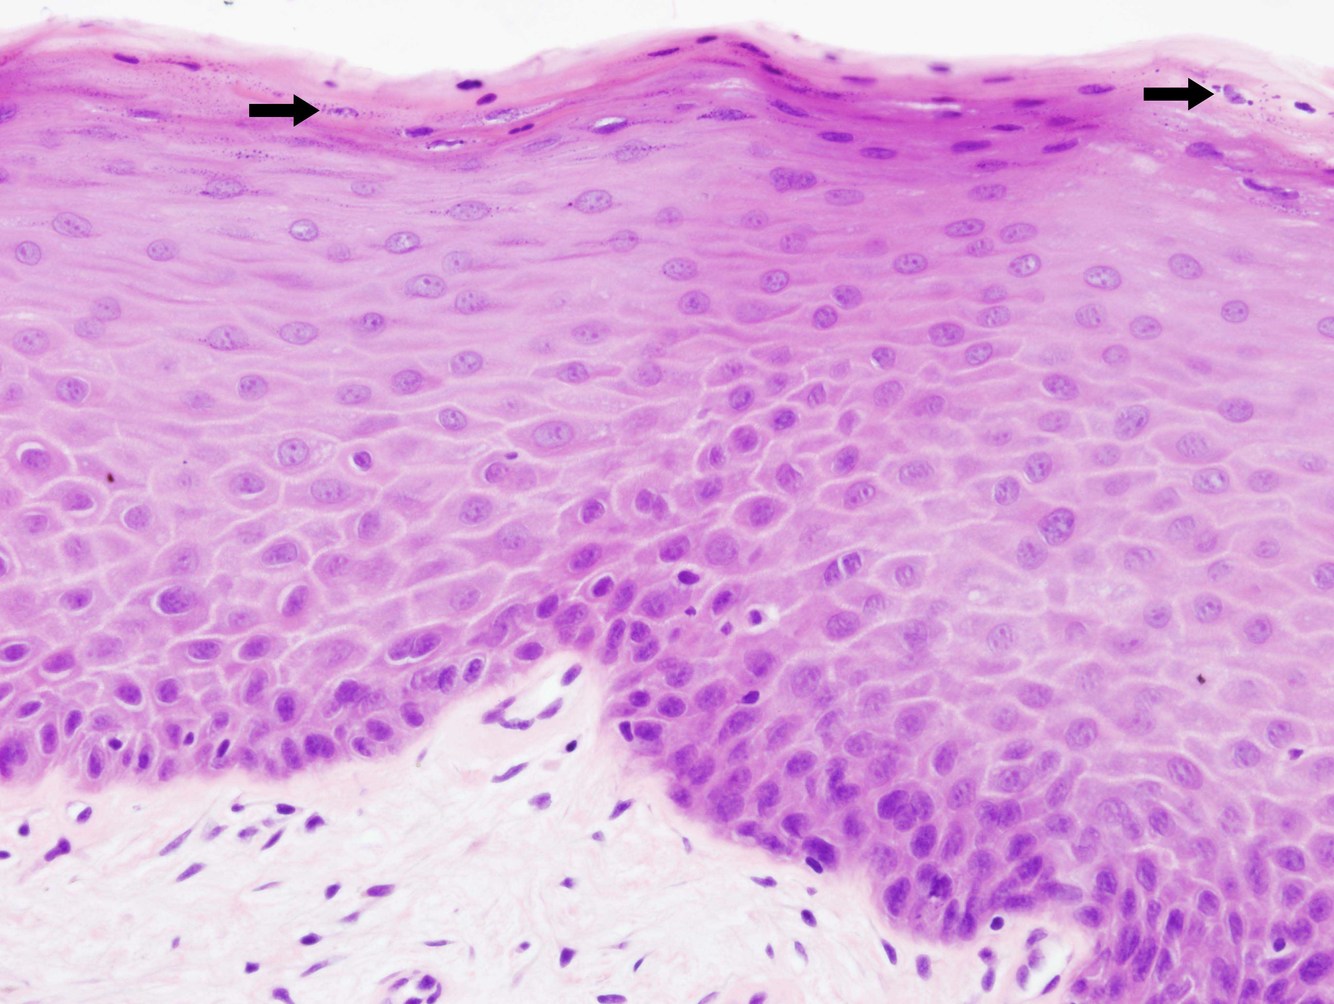

polymorphs attracted to stratum corneum creating munro micro abscesses.

parakeratosis, acanthosis and thick keratin scale

epidermal rete ridges are elongated and clubbed

what are munro micro abscesses

collection of neutrophils in the stratum corneum